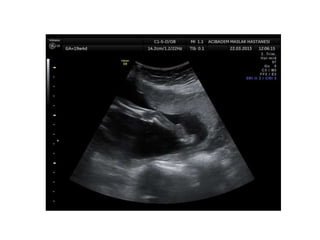

Arthrogryposis

•Multiple congenital joint contractures/ankyloses

involving two or more body areas

•Pena Shokeir phenotype

micrognathia, multiple contractures, camptodactyly

(persistent finger flexion), polyhydramnios

*many are AR

*Lethal due to pulmonary hypoplasia

Arthrogryposis •Multiple congenital jointcontractures/ankyloses involving two or more body areas •Pena Shokeir phenotype micrognathia, multiple contractures, camptodactyly (persistent finger flexion), polyhydramnios *many are AR *Lethal due to pulmonary hypoplasia • Distal arthrogryposis Subset of non-progressive contractures w/o associated primary neurologic or muscle disease